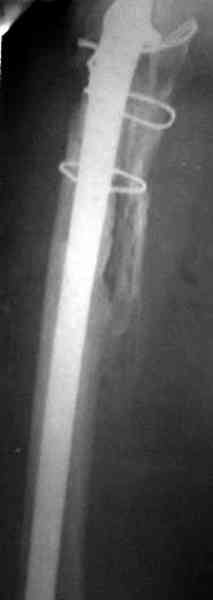

Представляю вашему вниманию снимки (прошу прошения за качество снимков) больной 48 лет с ревматоидным артритом, которой был сделан тотальный эндопротез справа,

контрольный снимок сделали только на 21день после операции (№1) и с интервалом 5 дней второй снимок (№2)

Судя по всему, произошел раскол наружной стенки бедра и ножка находится вне костного канала. В таком случае

решение одно - удаление ножки и установка новой в расчете на дистальную фиксацию. Конктреную модель подсказать тяжело из-за низкого качества Р-грамм.